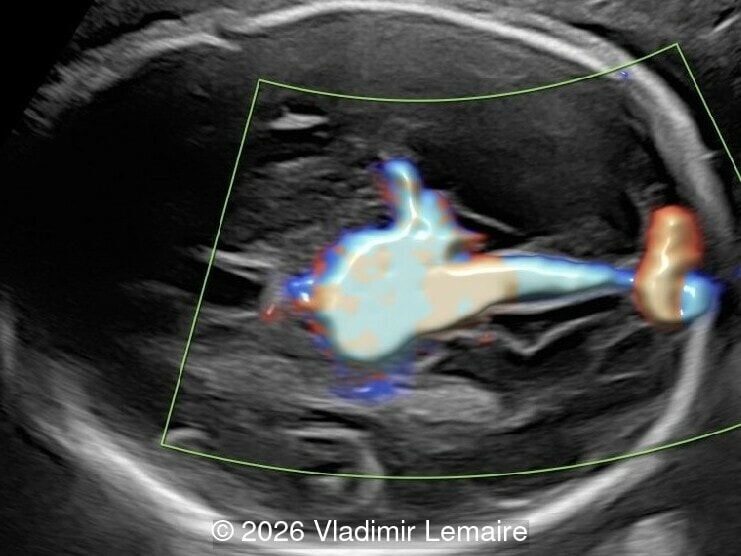

Intracranial arteries and veins in 3D color Doppler in combination with silhouette mode.

Image 4 Intracranial arteries and veins in 3D color Doppler in combination with silhouette mode.

Our imaging revealed enlargement of the fetal heart with dilation of the superior vena cava. On further evaluation, we identified an elongated anechoic cystic structure in the midline of the head, without mass effect on the surrounding structures. Color doppler demonstrated an arteriovenous fistula between the deep choroidal arteries and the embryonic median prosencephalic vein of Markowski. The vein of Galen aneurysmal malformation was likely the contributing factor to the cardiac enlargement. Cardiac function was, however, preserved and hydrops not present. Additional images are shown below.

On ultrasound, a VGAM appears as an elongated anechoic cystic structure in the middle of the head, often without mass effect on the surrounding structures. Color Doppler shows high-velocity flow in the lesion and can be used to identify the arteries feeding the vascular malformation. Pulsed-wave Doppler shows markedly turbulent flow. Additional key echocardiographic features include an enlarged heart with preserved systolic function, a dilated superior vena cava, and mild or moderate tricuspid regurgitation. Tricuspid regurgitation was not present in our case at the time of our evaluation.